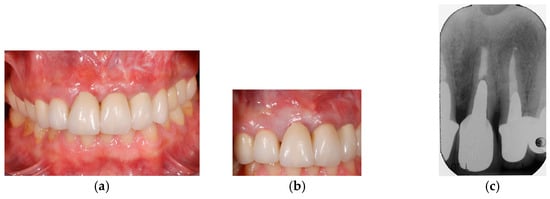

2.9. Clinical Cases and Study Diagram

- Lombardo, G.; Corrocher, G.; Pighi, J.; Mascellaro, A.; Marincola, M.; Nocini, P.F. Esthetic Outcomes of Immediately Loaded Locking Taper Implants in the Anterior Maxilla: A Case Series Study. J. Oral Implantol. 2016, 42, 258–264. [Google Scholar] [CrossRef]